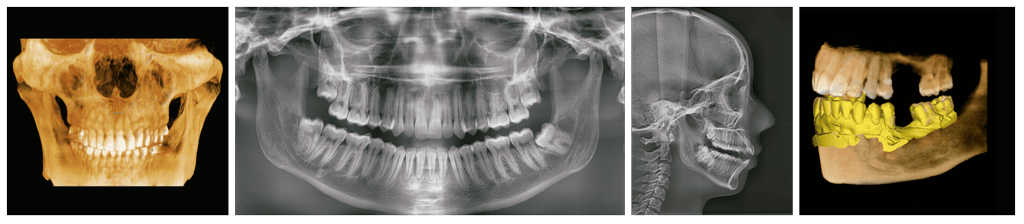

Green X incorpora pano, ceph (opcional), CBCT y escaneo de modelos.

Proporciona imágenes de alta calidad con menor radiación al combinar el procesamiento de imágenes con la amplia experiencia de Vatech en el campo de las imágenes dentales, mejorando la precisión de tu diagnóstico y una mejor planificación del tratamiento.

IMÁGENES

Tomografía

Panorámica

Lateral de craneo

Bitewing